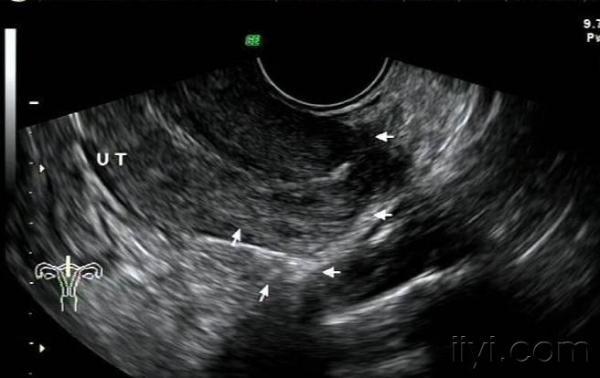

子宫穿孔超声表现图

子宫穿孔超声表现图,子宫穿孔超声图片

刚出炉的"子宫穿孔"1个 - 超声医学讨论版 - 爱爱医

子宫穿孔的超声诊断

超声诊断子宫穿孔并大网膜嵌顿1例

子宫穿孔彩超下表现

子宫穿孔彩超图